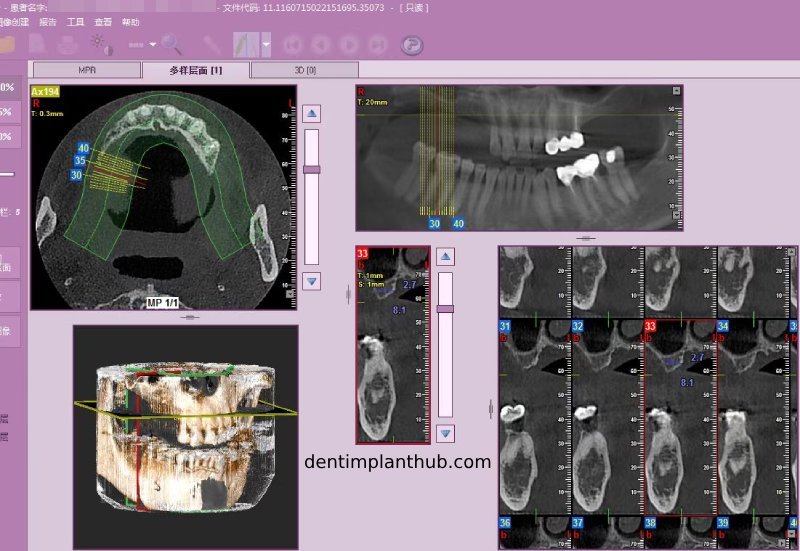

Screenshot of patient's CT on March 14, 2024